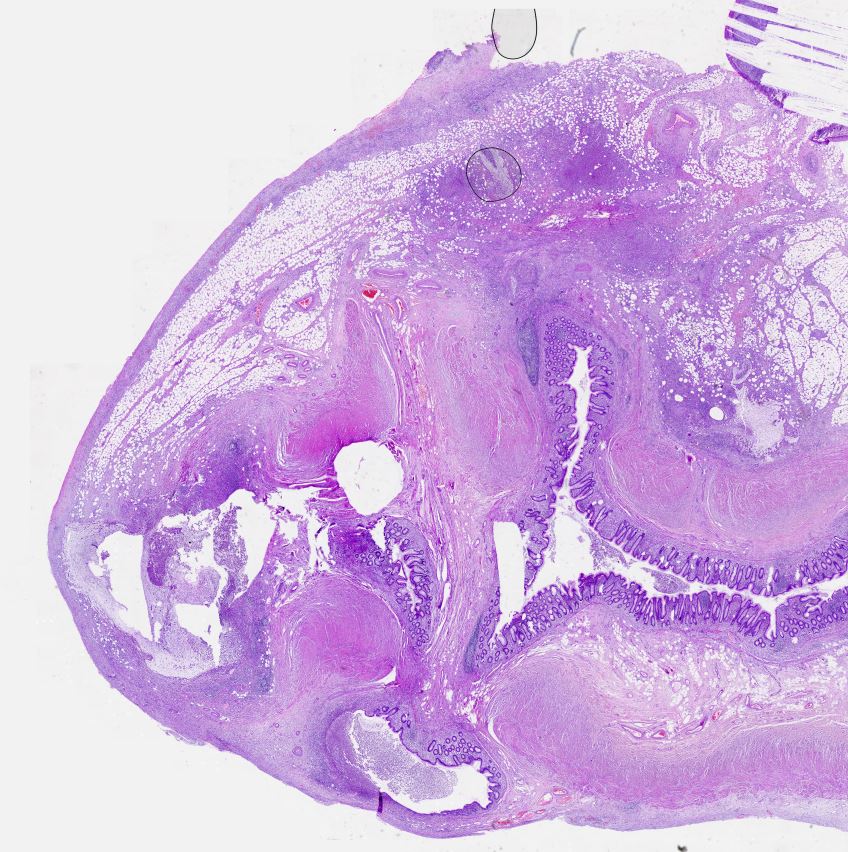

Oral skuamöz hücreli karsinom Oral skuamöz hücreli karsinom, keratinize. Likenoid displazi zemininde gelişmiş.